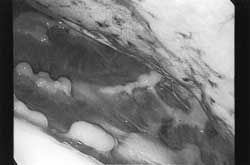

図5.プラークの肉眼所見

壁側胸膜面で肋骨の走行に沿うようにして白色調の表面平滑な大小のプラークを認める。